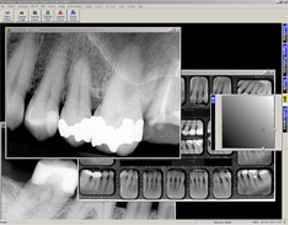

As a state-of-the-art dental clinic, we use digital dental radiography which minimizes x-ray radiation by 80%. Your radiographs (x-rays) are captured in a digital format and can be conveniently stored in your e-mail account. That’s right, no more carrying your x-ray films around.